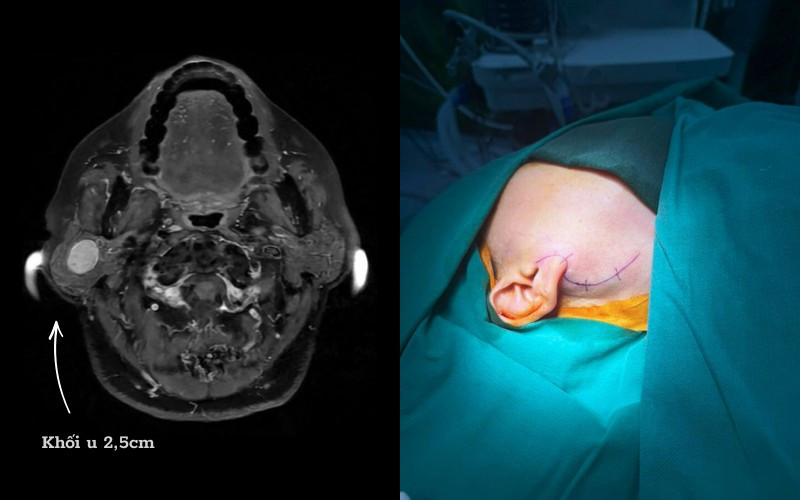

Trường hợp bệnh nhân D. là ví dụ điển hình, người bệnh phát hiện khối u tuyến mang tai phải từ nhiều năm trước, có biểu hiện sưng lệch vùng góc hàm, thỉnh thoảng đau tức. Dù đã được chỉ định phẫu thuật từ sớm nhưng bệnh nhân liên tục trì hoãn do lo ngại có nguy cơ liệt mặt sau mổ.

U tuyến nước bọt mang tai của chị D có vị trí phức tạp - Ảnh BVCC

Tiếp nhận thăm khám cho bệnh nhân D., ThS.BSNT Nguyễn Xuân Quang - Trưởng khoa Tai mũi họng và Phẫu thuật Đầu Cổ, Bệnh viện Đa khoa Hồng Ngọc cho biết, việc người bệnh trì hoãn điều trị trong thời gian dài khiến khối u tiếp tục phát triển, làm tăng nguy cơ chèn ép và tổn thương dây thần kinh mặt, điều này sẽ khiến ca mổ trở nên phức tạp hơn.